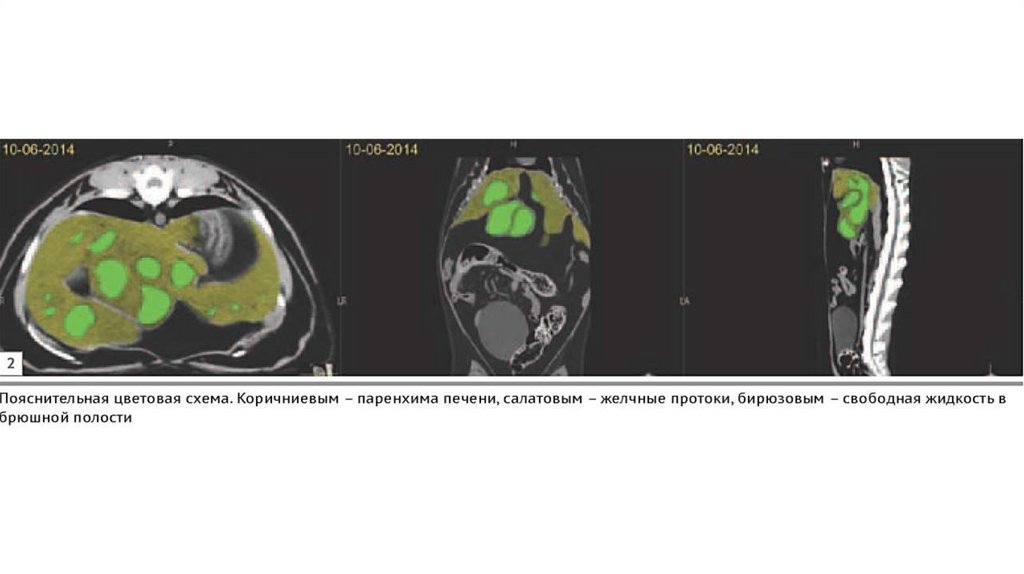

35.00M

9. Было проведено КТ для уточнения диагноза: